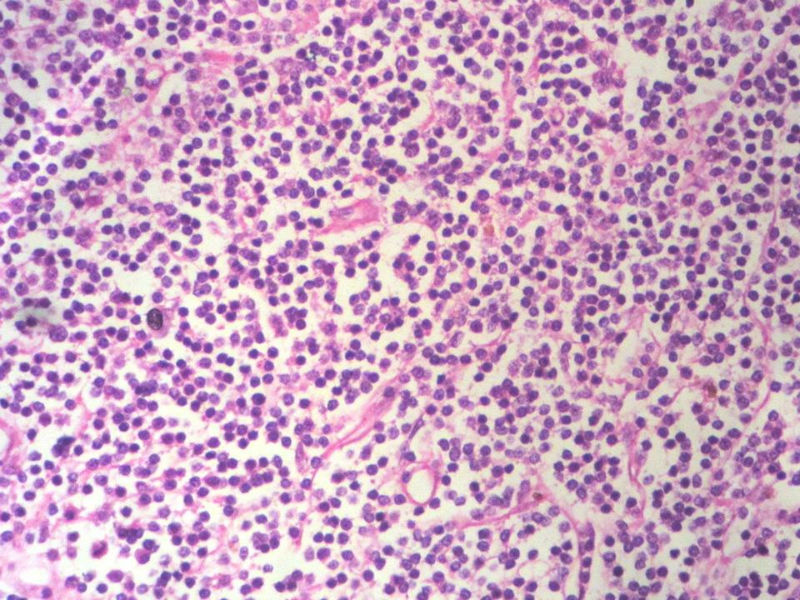

淋巴样细胞。细胞形态单一,细胞小。主要鉴别:

1)粘膜相关淋巴组织淋巴瘤

2)小细胞性淋巴瘤/慢性淋巴细胞性白血病

3)套细胞淋巴瘤

形态结构与细胞大小,似不支持滤泡性淋巴瘤。

HE:  1.MALT粘膜相关淋巴瘤:本例部位很特殊,位于“结膜下”,考虑MALT很合理;但本例镜下细胞形态很一致,诊断MALT是有难度的。

2. SLL小细胞淋巴瘤:就细胞形态而言,有相似之处,考虑SLL也有道理;但如果在没有发现淋巴结,肝,脾,骨髓或外周血具有病变的前题下,原发于结膜的SLL可能是少见的。

3.套细胞淋巴瘤:细胞大小及一致性比较符合;但本例核太规则了,套细胞淋巴瘤很难有这么规则的圆形或椭圆形。

本例是发生在特殊部位“结膜下”,HE肿瘤细胞形态形态一致,形似单核样B细胞。B细胞标记若明确阳性,诊断MALT是挺合理的。